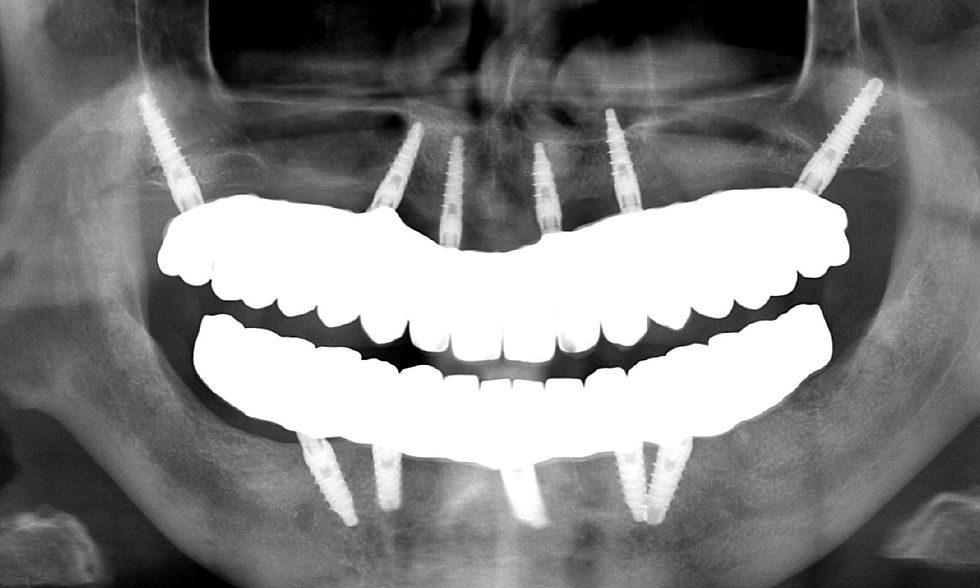

La morfologia convergente del collo Prama permette di recuperare la porzione di tessuto molle che con un impianto transmucoso tradizionale verrebbe occupata dal titanio del collo implantare. La convergenza di Prama fa sì che i volumi intorno alla porzione coronale dell’impianto vengano invece riempiti di coagulo e di importanti fattori di ricrescita, che si trasformano in tessuti molli spessi e funzionali.

L'ispessimento della gengiva che circonda il collo Prama rappresenta un beneficio indiscusso, soprattutto nei pazienti con biotipo più sottile, nei quali questo innovativo impianto apporta un ispessimento dei tessuti molli senza ricorrere a terapie rigenerative.

La stabilizzazione del connettivo, resa possibile dalla morfologia convergente e dalla microrigatura UTM, fa sì che tutto ciò che vi è al di sotto rimanga protetto e isolato da potenziali attacchi batterici, e che quindi l’osso si mantenga preservato in maniera efficace e a lungo, come ampiamente dimostrato dalla clinica.